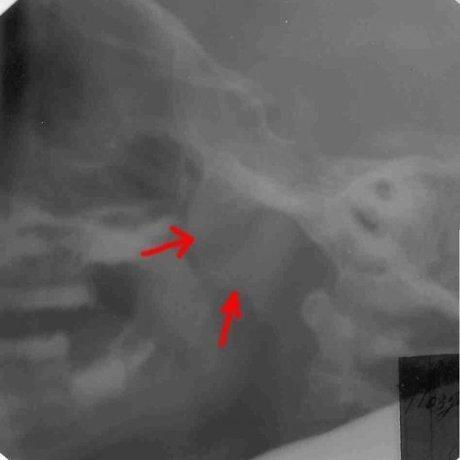

До лечения: у четырёхлетнего пациента аденоиды III степени.

После лечения аденоиды полностью рассосались и носовое дыхание восстановлено.

До лечения: на рентгене мы видим гигантские аденоиды, которые спускаются из носа в глотку. Пятилетний пациент не мог дышать носом.

После лечения носовое дыхание восстановлено и аденоиды рассосались.

Рентгенограммы, подтверждающие эффективность лечения, имеются только в нашей клинике и являются собсвтенностью доктора Сичинава.